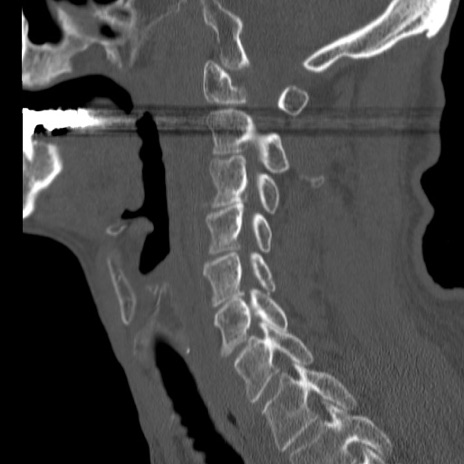

症例46 頚椎CT(矢状断像)

【症例】80歳代男性

【主訴】両側頚部〜上肢のしびれ

【現病歴】昨日、自宅内で転倒、その後より上記症状あり。意識障害なし。

【身体所見】両側上肢のallodynia(熱痛覚過敏)あり。MMTおよびDTRは正確な所見取れず。両上肢の挙上はなんとか可能。

異常所見と診断は?